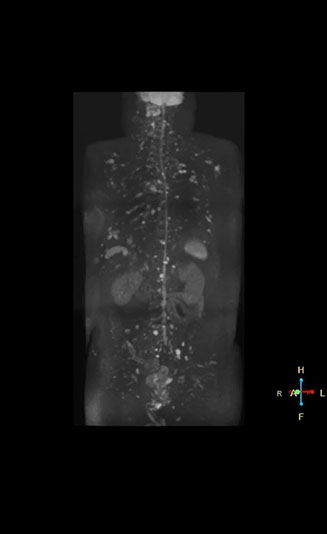

Radiologist Hiroshi Nobusawa, MD, PhD, explains that the coronal DWIBS protocol for whole body DWI is excellent for visualizing lesions in oncology patients. “About 90% of the DWIBS exams are done in this type of patients. The remainder of DWIBS exams are performed to gain information in cases of fevers of unknown origin,” he says. in image acquisition and postprocessing algorithms.”“mDIXON TSE sequences allow simultaneous characterization of morphological changes from the in-phase T2-weighted images and visualization of edematous changes, thanks to the water T2-weighted images from the same acquisition. Anatomical and morphological considerations could be a partial or complete ligament tear, a bony avulsion or hematoma.” “For soft tissue assessment mDIXON brings similar benefits. For example in one T2-weighted mDIXON TSE acquisition, having the multiple contrasts helps us assess abnormalities in peripheral nerves fascicles, which may be due to anatomical or inflammatory changes..” “In peripheral joints, we get good image quality in difficult areas with mDIXON TSE. Fat suppressed images appear homogeneous over the entire image, even with large coverage at 3.0T – for instance in scapular or hip girdles – or in the bearing areas or around metal prostheses*, where fat suppression is often deficient with STIR or spectral fat suppression, causing diagnostic difficulties. If a diagnostic image is right the first time, we don’t need to repeat or add a sequence.” “mDIXON TSE sequences allow simultaneous characterization of morphological changes from the in-phase T2-weighted images and visualization of edematous changes, thanks to the water T2-weighted images from the same acquisition. Anatomical and morphological considerations could be a partial or complete ligament tear, a bony avulsion or hematoma.” “For soft tissue assessment mDIXON brings similar benefits. For example in one T2-weighted mDIXON TSE acquisition, having the multiple contrasts helps us assess abnormalities in peripheral nerves fascicles, which may be due to anatomical or inflammatory changes..”

“The DWIBS sequence’s value in oncology cases is due to the high contrast it creates between lesions and surrounding tissue. Whole body DWI is requested by physicians who need to clarify TNM staging or determine therapeutic strategies, oncologists in need of diagnosis or follow-up scans, surgeons who need to see the presence of distant lesions that are sometimes difficult to detect by CT before surgery, and urologists for the evaluation of bone lesions, and the effect of chemotherapy and radiotherapy.”

“Switching to coronal DWIBS – rather than axial – further shortens scan time,” says Mr. Naka. “Important is that a dS SENSE factor of 5 shortens exam time while high image quality can be maintained, thanks to Ingenia’s dStream architecture.” He adds that the coronal orientation also avoids artifacts that are specific to combining axial images.

“When we use a coronal DWIBS acquisition, we can perform a full whole body examination, including other required sequences, within 30 minutes,” he says.